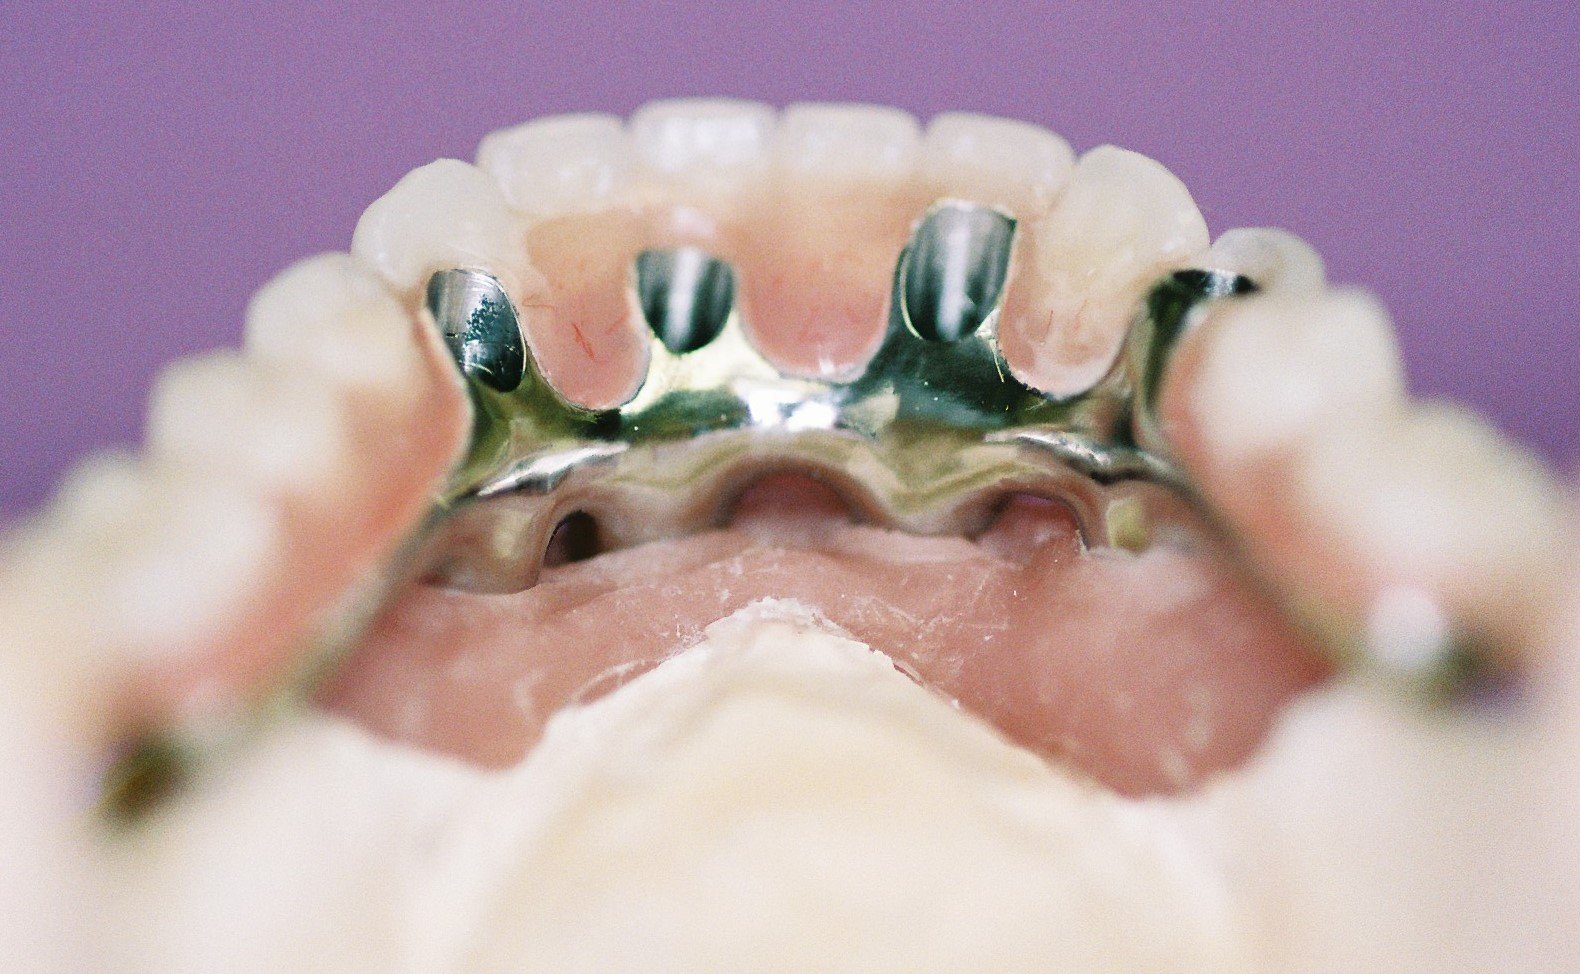

The underlying surface of the implant dentures with 4 nylon frictional sleeves in each denture.

-

This illustrates the lower zirconia implant denture with nylon friction sleeves along side a plaster model with titanium parallel abutments for a telescopic fitting Fixed-Removeable implant denture

This illustrates the upper zirconia implant denture with nylon friction sleeves alongside a plaster model with titanium parallel abutments for a telescopic fitting Fixed-Removeable implant denture.